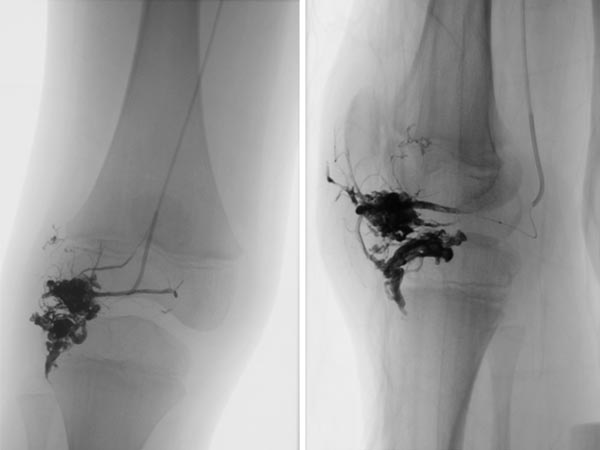

Abschluss-DSA-Bild (links a.-p., rechts seitliche Projektion) nach Beendigung der erneuten Embolisation zeigt wiederum angiographisch einen vollständigen Verschluss der beiden Anteile der AVM.